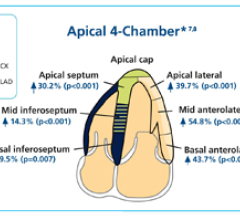

March 1, 2012 — Cell>Point announced it entered into a licensing agreement for South Korea, Taiwan, Malaysia, Vietnam and the Philippines with Hyun Imc Co. Ltd., headquartered in Seoul, South Korea, for the kit manufacture, marketing and distribution of Cell>Point’s cancer and cardiology nuclear imaging product.

February 29, 2012 — Lantheus Medical Imaging Inc. announced a strategic distribution arrangement for its Definity cardiac ultrasound contrast agent in the People’s Republic of China, including Hong Kong S.A.R. and Macau S.A.R.